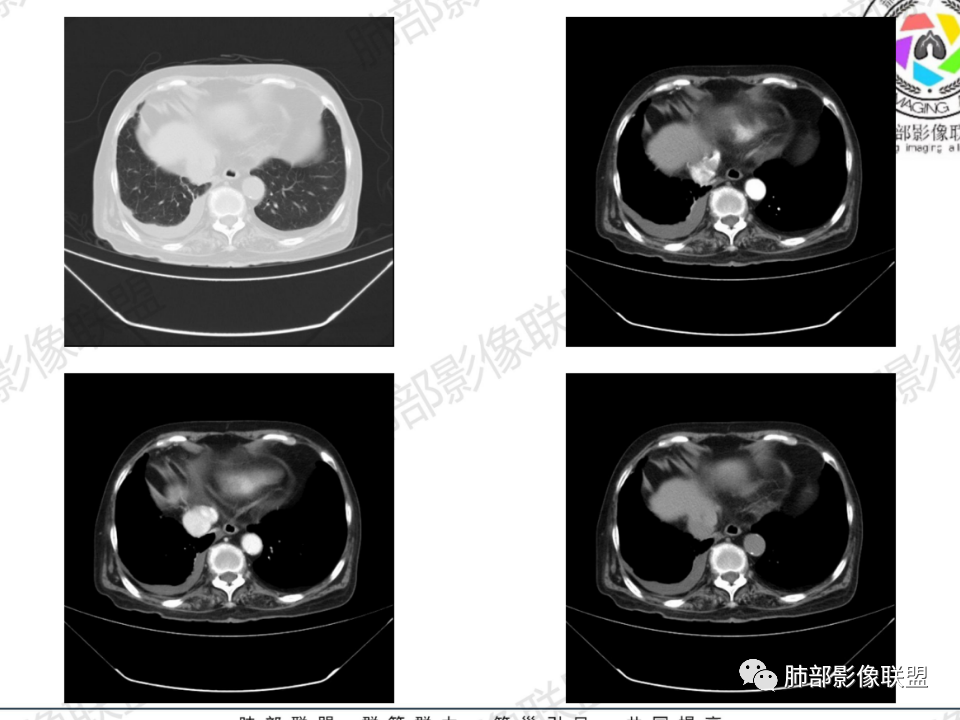

胸腔积液并胸膜钙化,符合结核;

相应上叶尖端及前段支气管开口未能追踪(阻塞),开口处见钙化。病灶渐进性强化,并衬托出较完整尖段及前段含液支气管影。支气管开口区域未见异常高密度强化(如类癌等)及相对乏血供区(如鳞癌)。病灶区未见液化坏死。右上纵隔及胸廓入口区未见病灶胸膜外突破(栽赃)。

右肺上叶后段等区域散在片状影,边界不清(提示渗出性病灶)。

纵隔及双肺门见钙化淋巴结。心包积液,右侧胸腔积液(提示存在活动新病灶)。双侧胸膜下见多发斑点状钙化,胸廓变形(提示存在结核基础病变可能)。 诊断意见:综上,右肺上叶块状影更符合继发性肺结核。 最后小结:既往诊断淋巴结结核,提示已治愈。近2年服用激素,可疑诱导结核复燃,也可引起发热。纵隔肺门淋巴结肿大钙化,压迫支气管,右肺上中下叶支气管均狭窄,所以引起喘息咳嗽。尖段支气管受累闭塞,导致肺不张、支气管粘液栓,出现条状无强化区。病变累及胸膜,导致结核性胸膜炎并胸水,引起右侧胸痛。实验室检查血沉快,CA125高,低蛋白,均符合结核。下一步,建议支气管镜尖段支气管刷检并抗酸染色。(本段摘自於雄老师精彩发言)